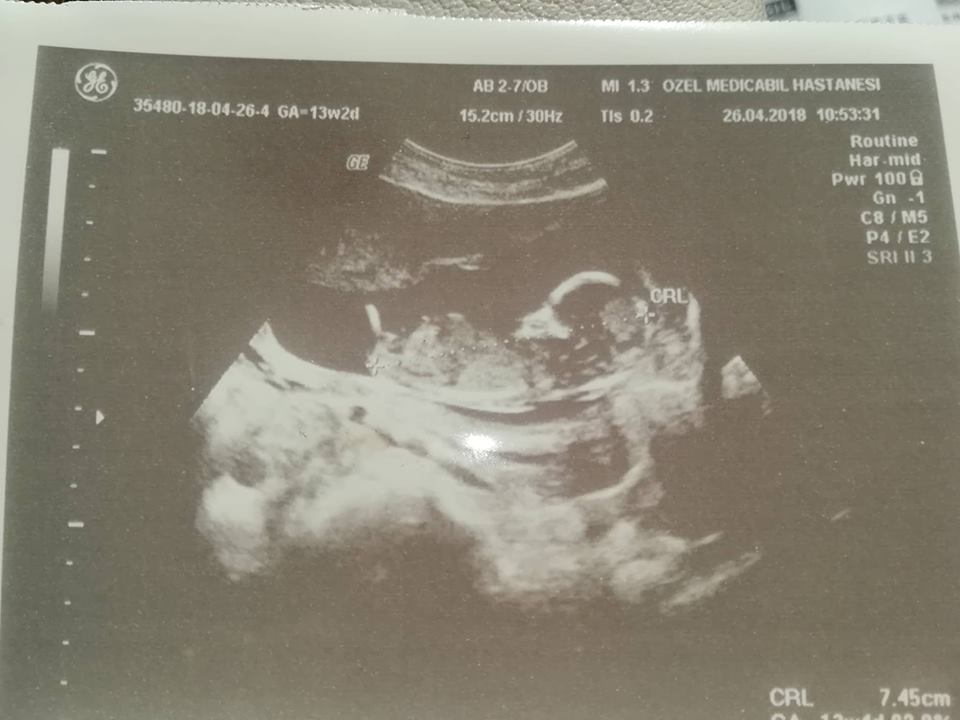

Nub teorisiyle cinsiyet tahmini bebeğim erkek mi kız mı ?

Bebeğinizin cinsiyetini emin olmamakla birlikte erkeğe benzettim.Bu haftalarda yanılma payı çok yüksek. Bebeğinizin cinsiyetini 17-19 ve 20 haftalarda net olarak öğrenebilirsiniz.

Allah hayırlısını nasip etsin. Daha önce dediğim gibi bu haftalarda yanılma payı çok olur. Net olarak 17-19-20. haftalarda bebeğinizin cinsiyetini öğrenirsiniz. Sağlıklı gebelik geçirmeniz dileği ile..

Nub teorsisi için cinsiyet tahmininde yorum isteyen arkadaşlar lütfen uyarımızı dikkate alın. Ultrason görüntüleri elinize ilk verildiği gibi net olmaz. Sık sık ışığa maruz kaldığı için görüntü kalitesi bozuluyor dolaysıyla bizlerde değerlendirme yapamıyoruz. Sizlere yorum yapabilmemiz için görüntü kalitesi aşağıdaki linkte yer alan görseller gibi olmalıdır. Ayrıca Bebeğin cinsiyeti net olarak 18-19-20. haftalarda belli olur.. Nub teorisi ile cinsiyet nasıl belirlenir ?